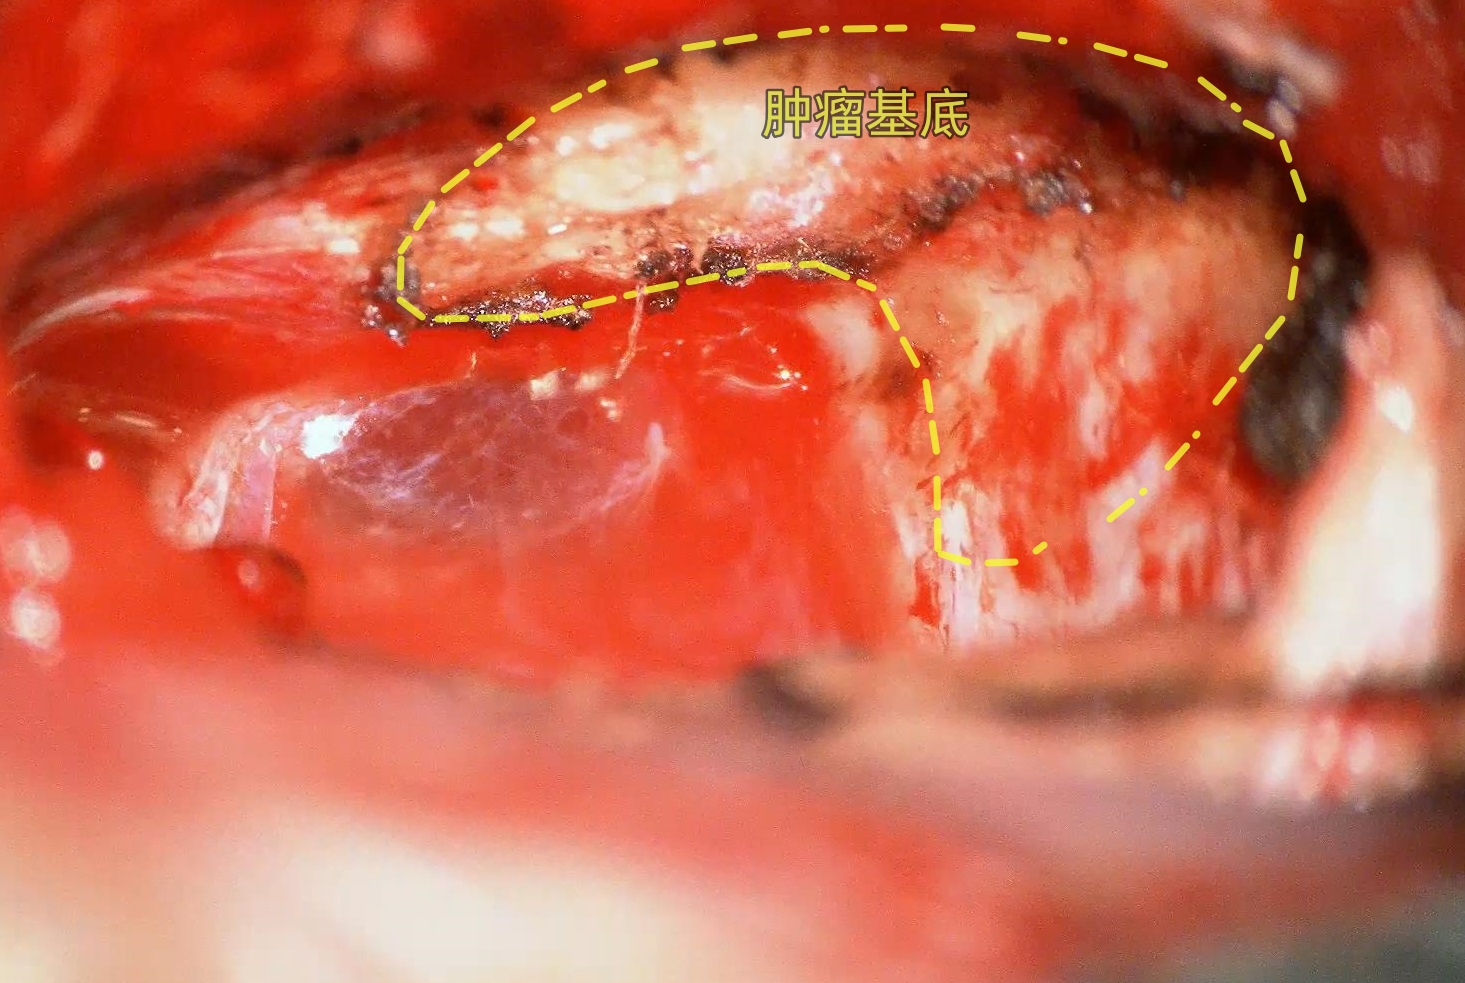

采用C形切口,打开硬膜即可见肿瘤位于横乙角,基底附着于岩骨侧壁 以及 小脑幕,肿瘤与小脑有明显分界,易于分离。肿瘤全切后可见面听神经、后组颅神经表面的蛛网膜界面完整。属于蛛网膜外完整切除肿瘤。全程监测Ⅴ-Ⅶ-Ⅹ-Ⅺ颅神经自由肌电图。术后患者无相关并发症。